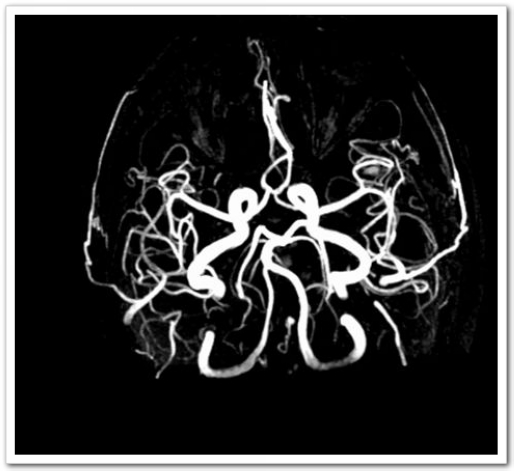

60歲的張阿姨這天正在家中看電視,突然感覺(jué)自己右側(cè)上肢使不上勁,主要為右手拿不穩(wěn)東西,日常生活動(dòng)作突然不能像平時(shí)那樣完成。真是人在家中坐,病從天上落,癥狀持續(xù)無(wú)明顯緩解,也無(wú)進(jìn)一步加重,遂至深圳大學(xué)總醫(yī)院神經(jīng)內(nèi)科就診。入院后頭顱CT排除腦出血;顱腦磁共振平掃M(jìn)RI+MRA:1.左側(cè)頂葉皮層急性腔隙性梗死灶。2.雙側(cè)額、頂葉皮層下少許缺血灶。3.頭顱MRA未見(jiàn)血管異常。

圖1:MRI:左側(cè)頂葉皮層急性腔隙性梗死灶